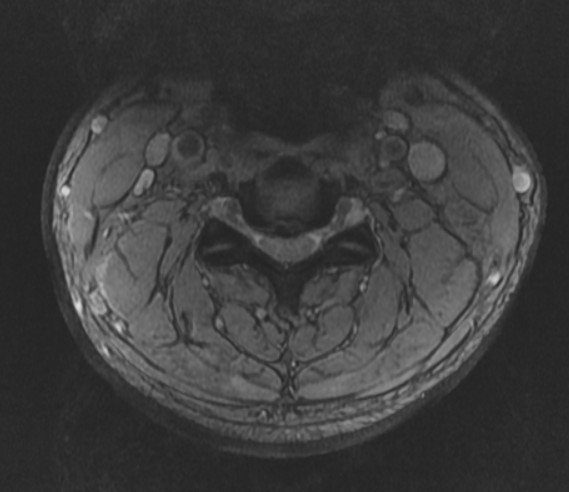

再次到大醫院檢查,照了X光、CT、MRI似乎追到問題了